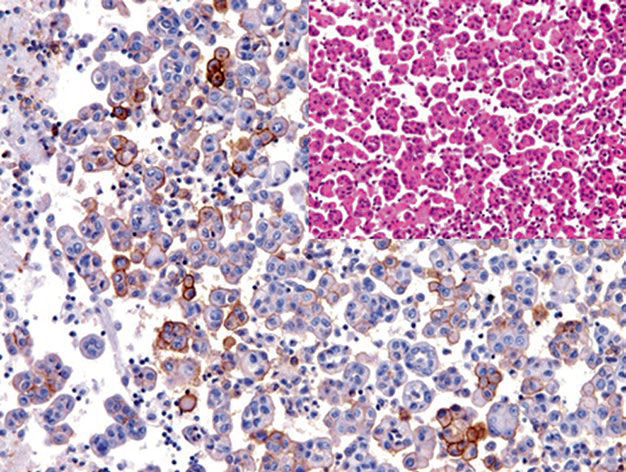

图2. 恶性胸腔积液中,间皮瘤细胞CD141阳性。

图4. 恶性间皮瘤表达IMP3。